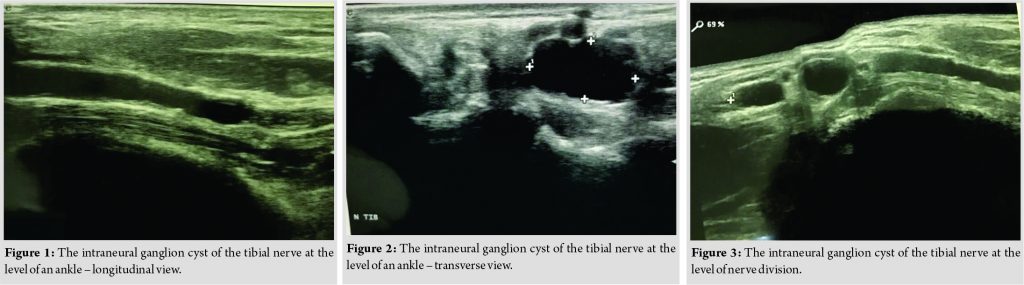

An X-ray of the foot showed no abnormalities. On an ultrasound examination of the foot, the longitudinal and transverse views were taken using a linear 14MHz probe, Esaote My lab Class C. The patient was kept in the horizontal (lying) position. The ultrasound examination showed that the patient had an intraneural ganglion cyst of the tibial nerve at the level of an ankle and the nerve division to the medial and lateral plantar nerves (Fig. 1, 2and 3).The nerve conduction study suggested a slower conduction of the tibial nerve.